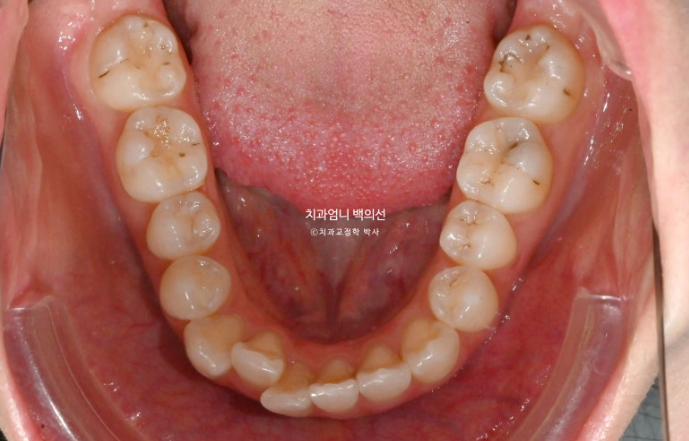

25.01

위 아래 치아중심선이 어긋나 있고 아래 앞니 하나가 솟으면서 뒤로 들어가 있습니다.

어금니 교합은 좋죠.